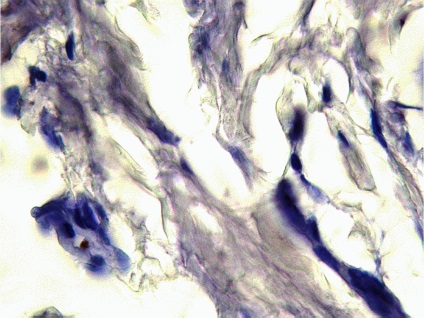

Ábra. Immunhisztokémia 11: CD-31 expressziója a vaszkuláris endotéliumon, a bőrben a haemangiomatosis

Következtetés (patológus MD Karev VE): egy jóindulatú daganat tömegének faggyúmirigy; haemangiomatosis bőrben, cutan vasculitis (gyulladásos elváltozások érfalak).